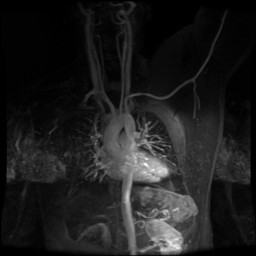

RADIOLOGY: CHEST: Case# 34548: NORMAL STUDY. A 40 year-old left hand dominant male presents with complaints of left arm pain and left hand numbness when the left arm is in certain positions.